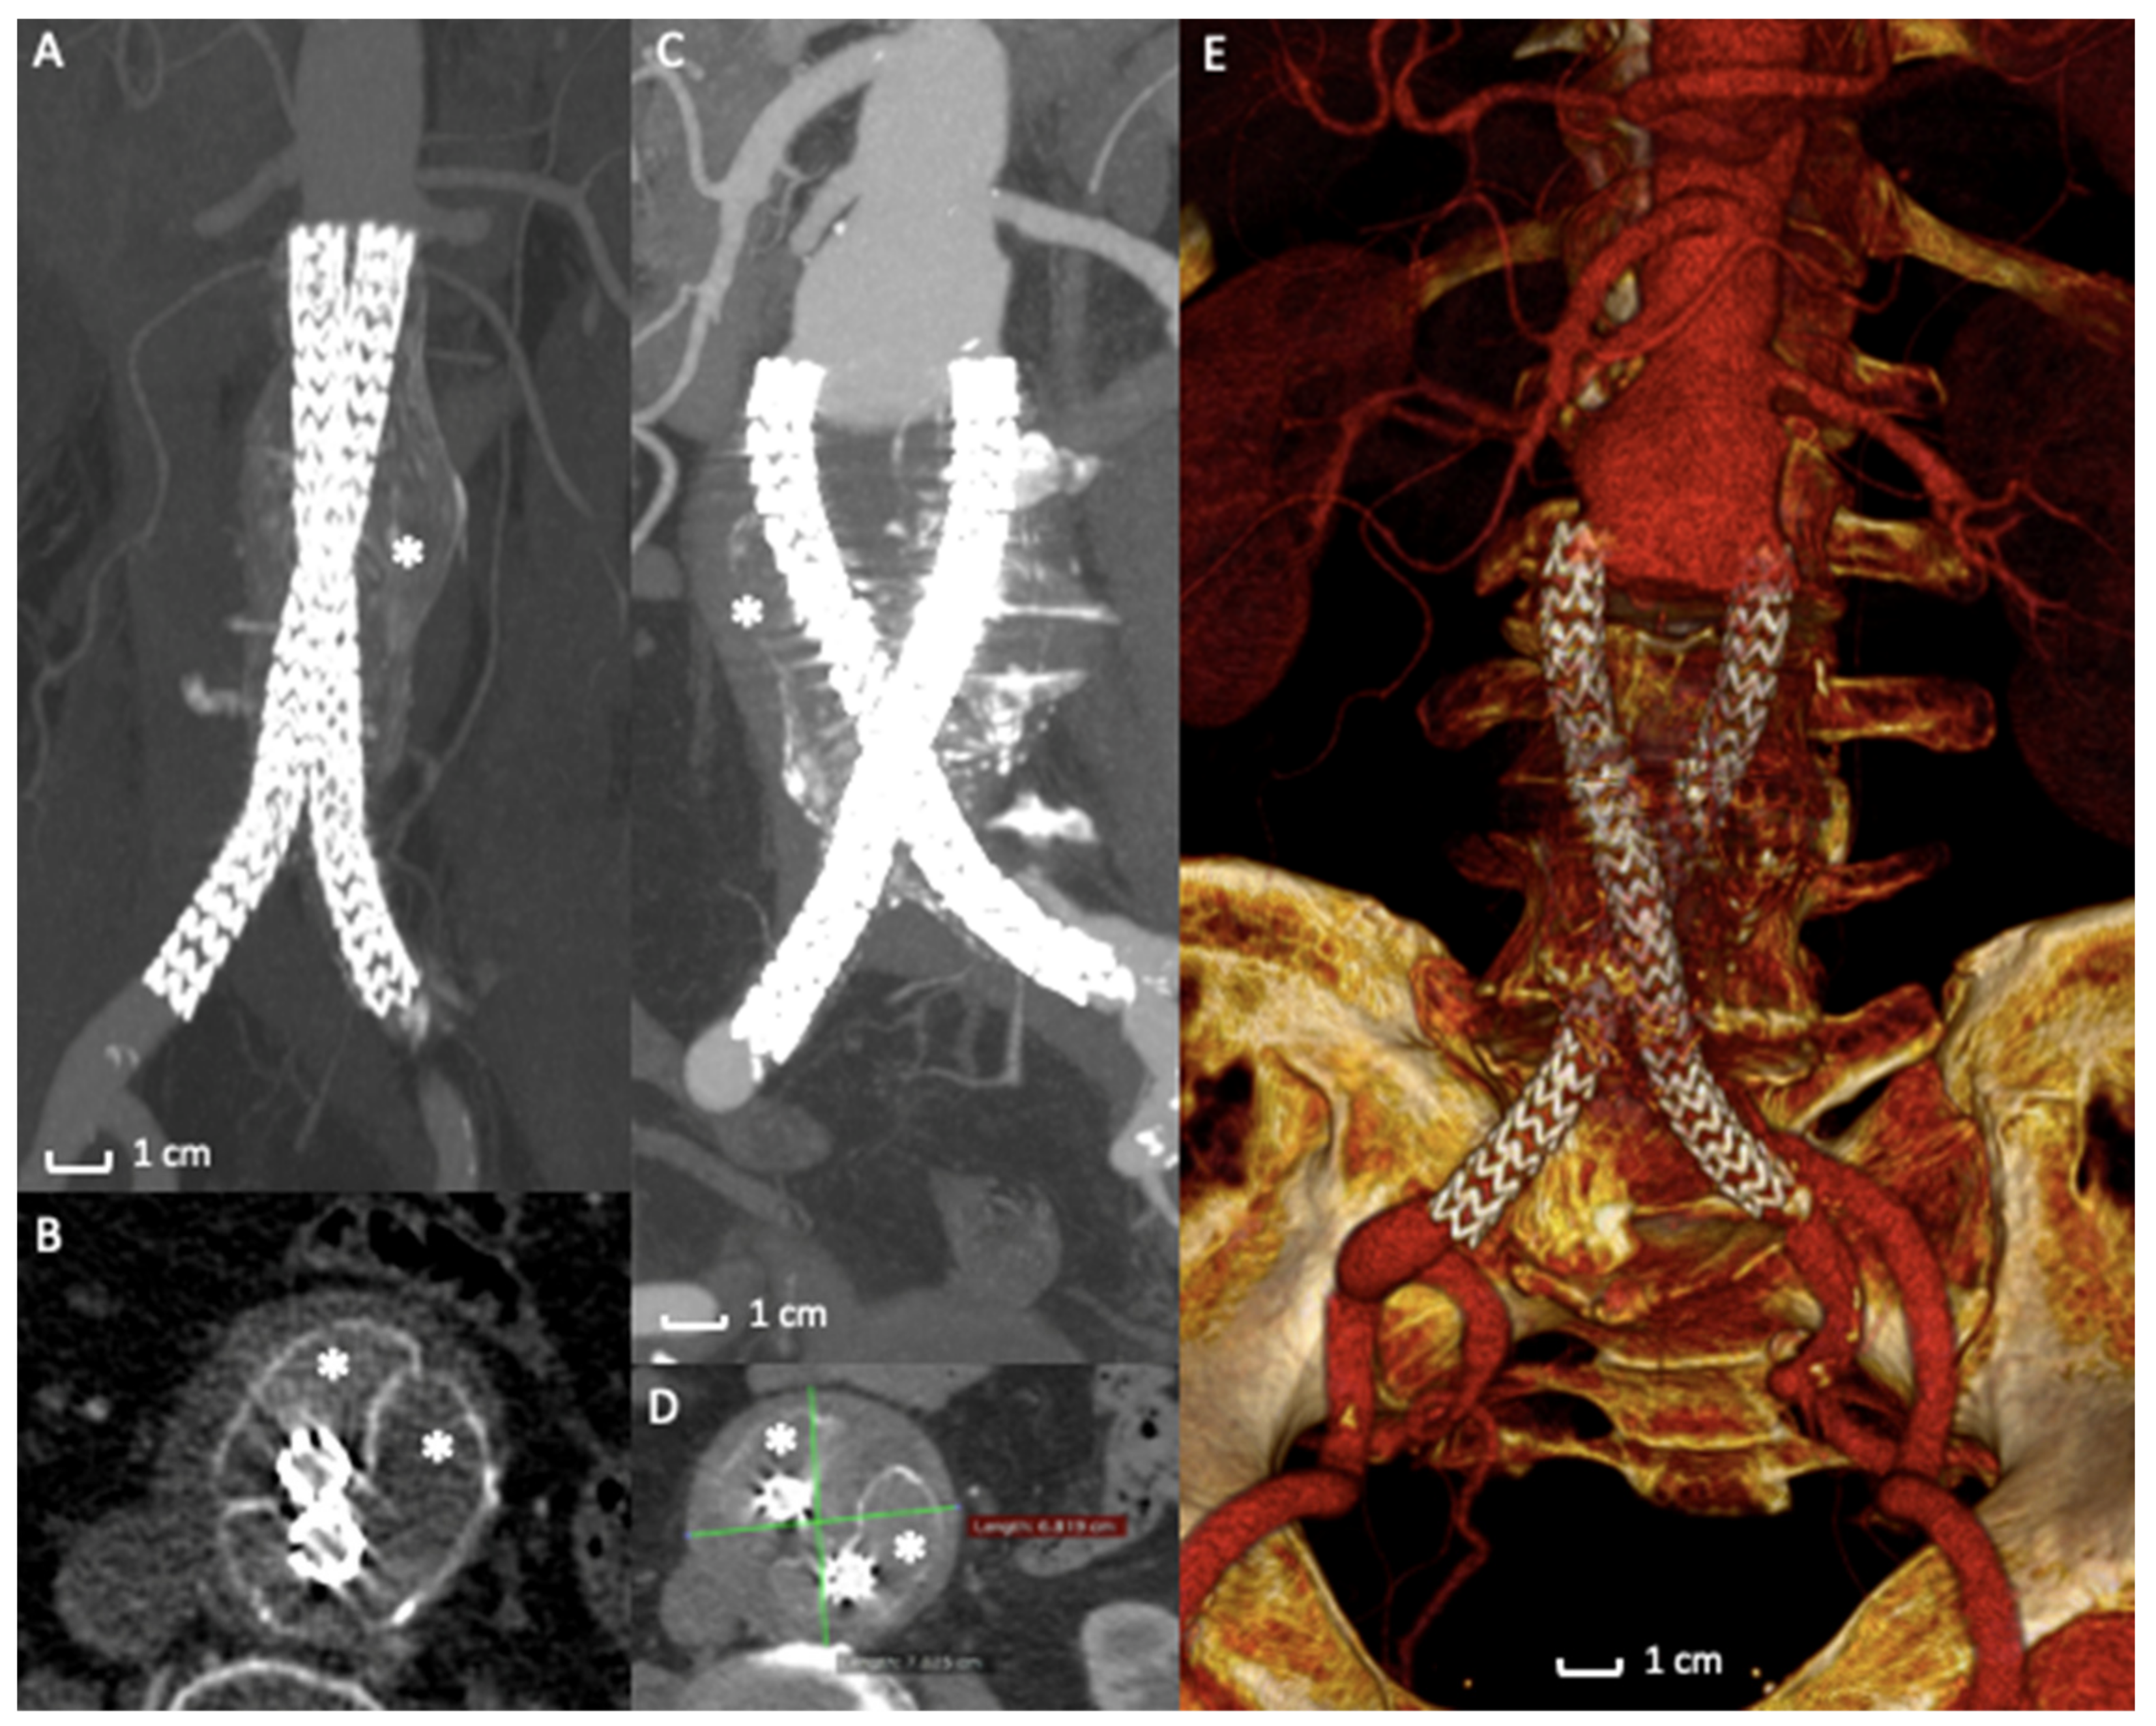

In a retrospective analysis [66] of prospectively collected data of 295 cases of endovascular aneurysm sealing using the Nellix device for abdominal aortic aneurysm, therapeutic failure was seen at a surprising and alarming rate of 33.2%. The most common failure mechanism was the stent graft migration associated with type IA endoleak and sac expansion, as demonstrated by a recent systematic review (Figure 4A–E) [58]. In several cases of failure, stent grafts were explanted from the patients’ bodies with a significant open vascular intervention. EVAS failures were also responsible for AAA rupture with severe or fatal consequences for the patients. In case of graft explantation, surgeons noted that the bags containing polymer were still intact, the polymer was not leaking into the vasculature, and maintained the expected consistency. The cause of failure was reported to be the lack of a stable proximal fixation of the entire device into the aneurysm sac [67,68,69].

Figure 4.

Case of Nellix Endograft Failure due to distal migration. (A) Computed Tomography Angiography detail of a Nellix endograft implantation. The asterisk (*) indicates the polymer filled endobags that correctly seal the aneurysm sac. (B) Axial view of the same exam highlights the correct stents’ and endobags’ configuration, asterisks (*) mark the two endobags adapted to the aneurysm sac. (C) Computed Tomography Angiography detail of the 2-year follow-up exam revealing a distal migration of the entire system (arrows) with AAA enlargement (D) and endobags dislocation (*). (E) 3D volume rendering of Computed Tomography Angiography of the endograft migration and failure, requiring open surgical conversion.